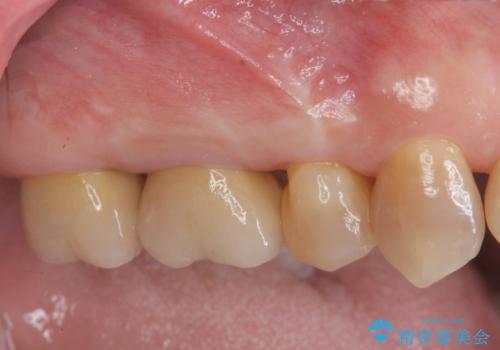

装着されているクラウンを除去し、自然な色調のジルコニアクラウンによる審美生の改善、インプラントを用いた欠損部の機能回復を計画します。

自然な仕上がりとインプラントによる咬合機能の回復に満足いただくことができました。

- 88万円(インプラント・チタンカスタムアバットメント・ジルコニアクラウン×4・仮歯×4)費用は治療当時の料金となります